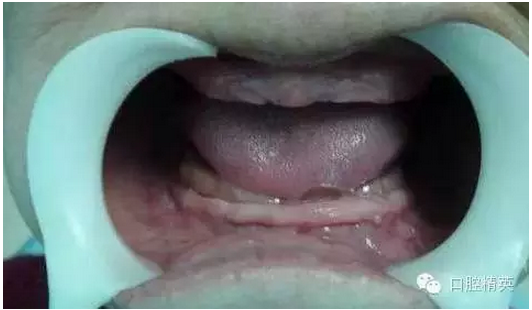

患者口內(nèi)的牙槽脊情況